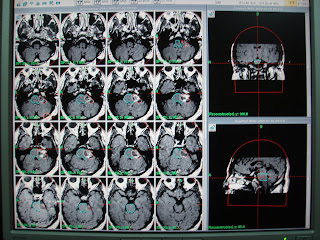

This 32 years old gentleman from Lahore was a diagnosed case of left Acoustic Schwannoma.He presented with progressive left hearing loss since 10th June 09, left hemi facial numbness, mild headache , loss of taste and occasional imbalance since 20 days. Clinical examination revealed left hemi facial hypoesthesia and poor corneal reflex. MRI shows heterogeneously enhancing mass in left CPA. He was treated with marginal dose of 12.5 Gy at 50% isodose line to the target volume of 9.0 cc. Multiple isocenters with 14,  8 and 4 mm collimators were used in APS mode. He was discharged on tapering doses of Dexamethasone and advised for follow up images after 6 months.

F.Up at 2 yrs. Shows 90 % reduction in tumor.